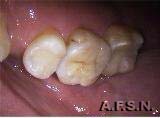

ANTES DEPOIS

O caso acima ilustra uma substituição de restauração de amálgama por um INLAY Artglass ( 1º molar) e restauração em resina composta no 2º molar.